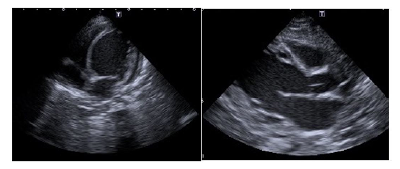

On admission to the tertiary PICU, laboratory tests were performed (Table 1). Platelets and fresh frozen plasma were administered for thrombocytopenia and prolonged prothrombin time. The patient was initially treated empirically with ceftriaxone and later with piperacillin-tazobactam and linezolid due to fever and elevated analytical inflammatory parameters. During hospitalization, she was systematically evaluated by Pediatric Cardiology. Serial echocardiograms were performed and showed no structural abnormalities despite reduced left ventricular ejection fraction (LVEF = 22%) and enlarged ventricles with a maximum left ventricular diameter of 41 mm (Figure 1). The patient presented with refractory hypotension despite optimization of inotropic support (dopamine 14 mcg/kg/min, adrenaline 0.4 mcg/kg/min, and milrinone 0.5 mcg/kg/min).

Figure 1 Transthoracic echocardiogram (apical and parasternal long-axis views) showing cardiomegaly and left ventricle dilation.